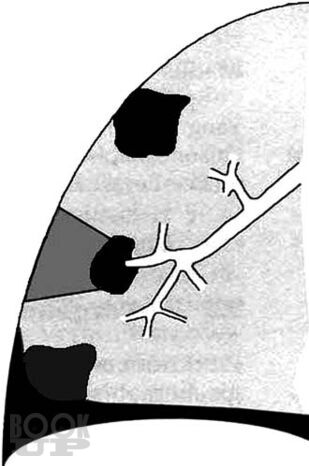

В книге в практическом аспекте изложены вопросы ультразвуковой диагностики опухолей лёгких: показаны возможности и ограничения трансторакальной эхографии при выявлении внутрилёгочных объёмных образований, приведена методика исследования и нормальная эхокартина грудной клетки, подробно освещена ультразвуковая семиотика центрального и периферического рака лёгкого, включая эхопризнаки про# растания опухоли ворганы средостения или грудную стенку. Детально изложены вопросы дифференциальной диагностики онкологической патологии лёгких при синдроме безвоздушной лёгочной ткани и синдроме пристеночного образования. Впервые представлен комплекс симптомов для определения внутри- или внелёгочной локализации пристеночного образования. В отдельной главе рассмотрены субплевральные очаговые образования неопухолевой этиологии: инфаркт лёгкого, очаговый фиброз, жидкостные кисты, артериовенозная аневризма и другие редкие заболевания. Книга иллюстрирована большим количеством эхограмм, отображающих основные диагностические признаки рассматриваемой патологии.